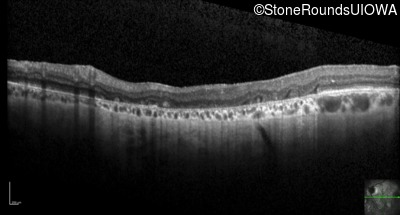

Optical Coherence Tomography - Right - 20/100 +1

Exemplar / OCT Stack